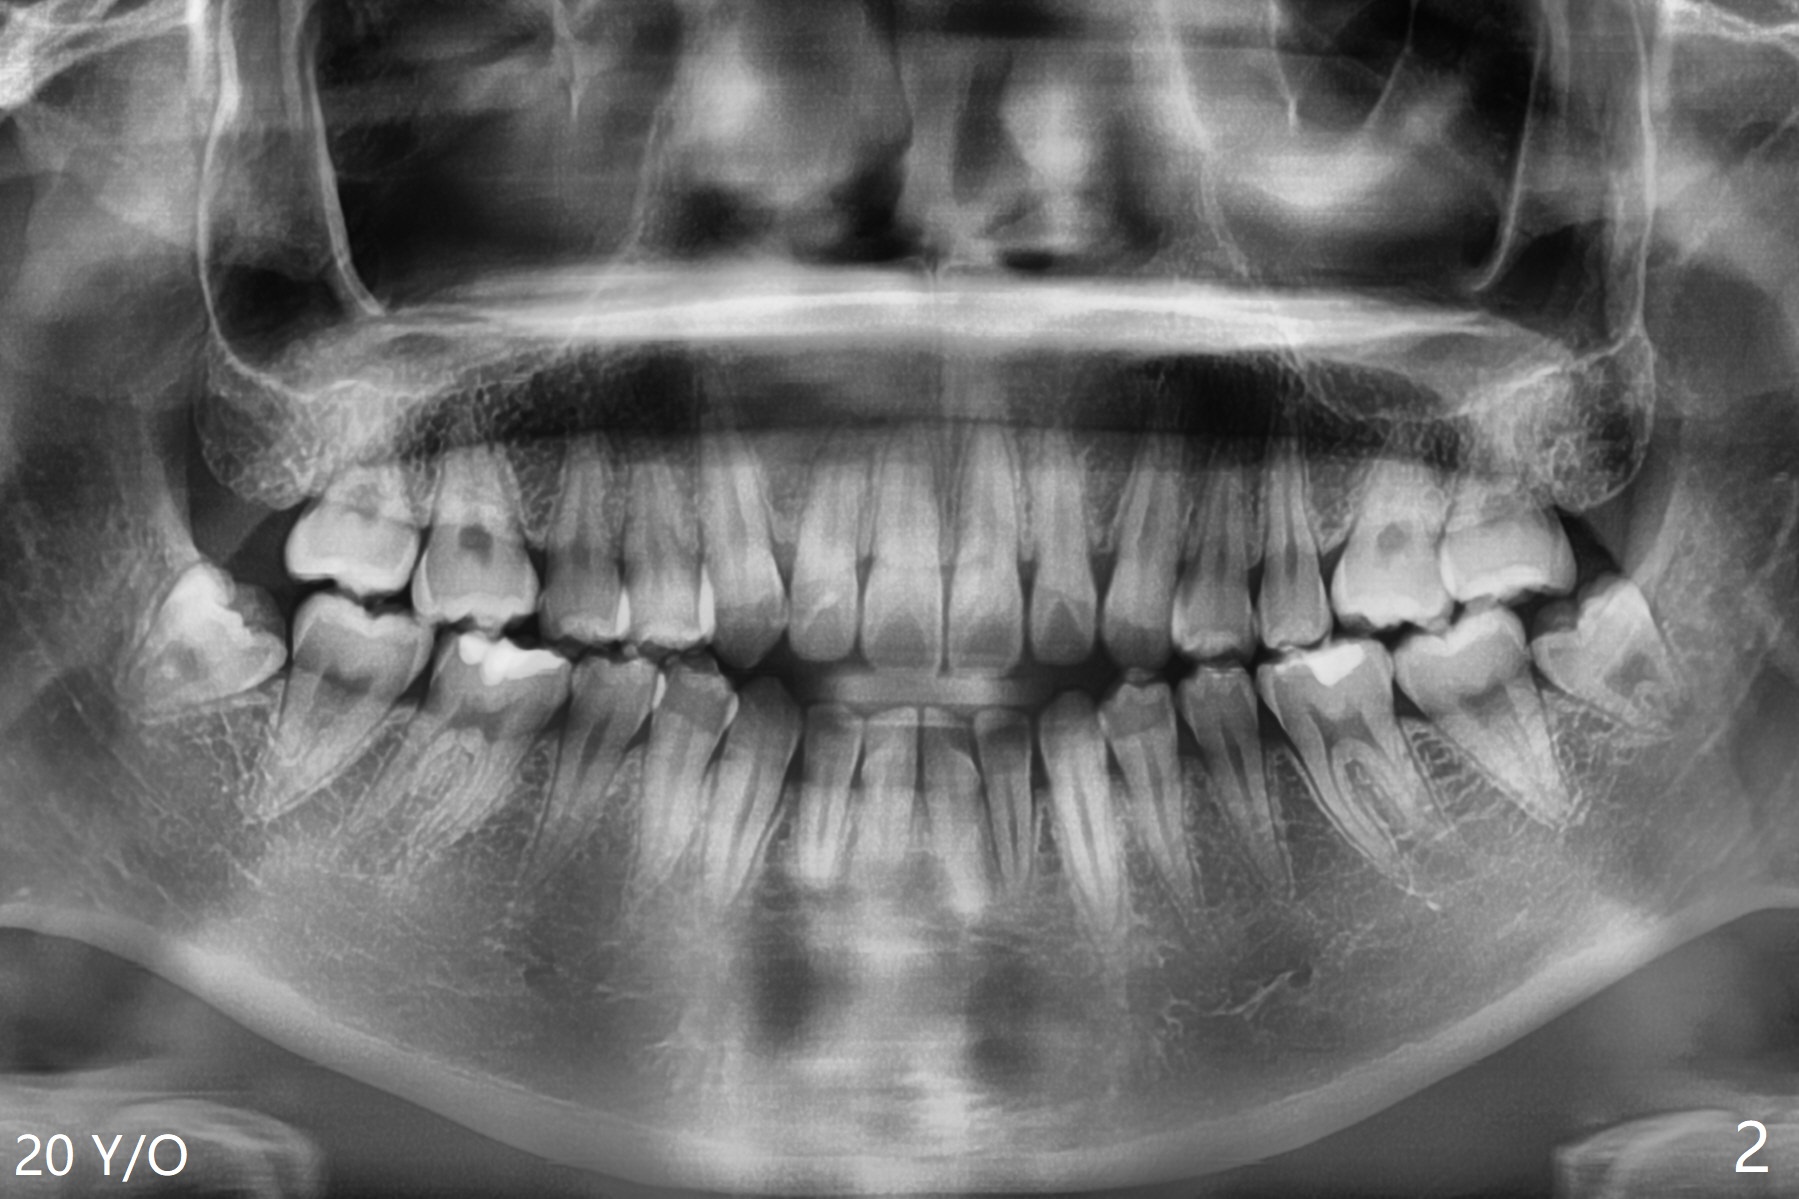

The teeth #17 and 32 are developing at the age of 11 of a woman (Fig.1). She requests extraction at the age of 20 (Fig.2 (anterior open bite)). While buccodistal trough is created for both of them, the one at #32 needs a sectioning before removal. Osteogen plug is applied for both of them. Postop hemorrhage occurs at #32 for 2 days.